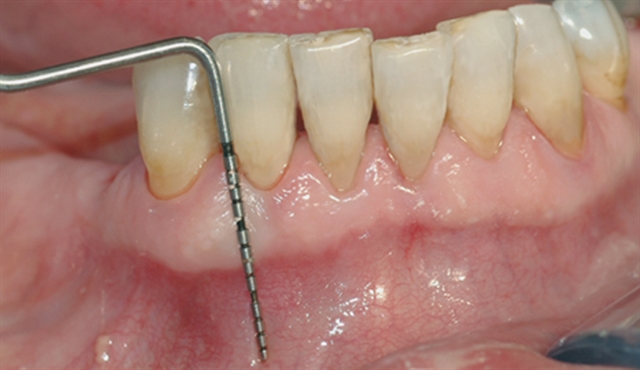

Bildet viser tilsynelatende normale tannkjøttsforhold ved tenner i underkjeven.